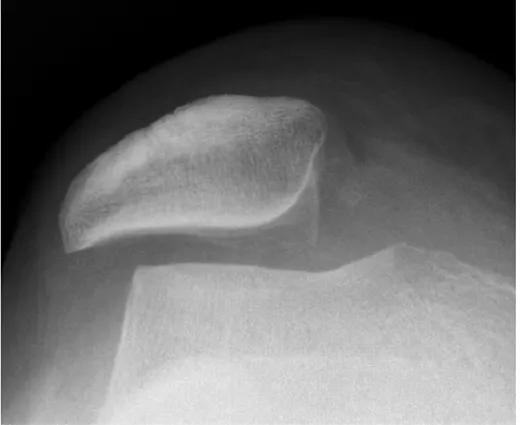

我们很多朋友啊,出现膝关节疼痛的时候,往往到医院想先用简单的检查发现问题,比如拍一张普通的膝关节X线片子,但是谢医生要告诉大家,一张最基本的膝关节正侧位片子,对于髌骨发生的倾斜等情况提供的信息量是非常少的,此时如果我们想要进行X线检查,那么进行膝关节的髌骨轴位像,往往是一个比较好的选择,通过这张X线片子,我们可以发现髌骨是否发生了倾斜或者是外移,但是有一个缺点,是我们不知道软骨到底磨损到了什么样的程度,关节内其他结构是否存在着损伤?

那么有些朋友会说做CT是否可行? CT检查一样确实可以发现髌骨是否有明显的异味,同时也能发现骨与骨之间是否有明显的磨损,但是同样有一个缺点,CT无法发现关节内的软骨磨损程度,关节内的半月板等其他结构是否存在问题?